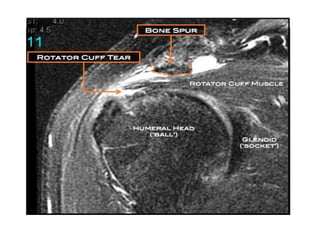

MRI

• A patient with symptoms of

subacromial impingement may show

increased signal in the supraspinatus

tendon on T2-weighted MRI consistent

with tendinopathy;

• Increased fluid in the subacromial

bursa also is a sign of subacromial

impingement.

MRI • A patientwith symptoms of subacromial impingement may show increased signal in the supraspinatus tendon on T2-weighted MRI consistent with tendinopathy; • Increased fluid in the subacromial bursa also is a sign of subacromial impingement.